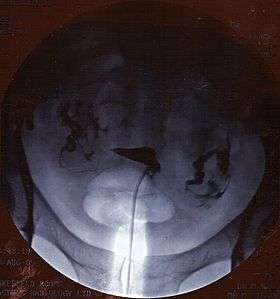

![]() A normal hysterosalpingogram. Note the catheter entering at the bottom of the screen, and the contrast medium filling the uterine cavity (small triangle in the center). | |

Hysterosalpingography (HSG) is a radiologic procedure to investigate the shape of the uterine cavity and the shape and patency of the fallopian tubes. It entails the injection of a radio-opaque material into the cervical canal and usually fluoroscopy with image intensification. A normal result shows the filling of the uterine cavity and the bilateral filling of the fallopian tube with the injection material. To demonstrate tubal rupture, spillage of the material into the peritoneal cavity needs to be observed. A synonym to hysterosalpingography is uterosalpingography.

The test is usually done with radiographic contrast medium (dye) injected into the uterine cavity through the vagina and cervix. If the fallopian tubes are open the contrast medium will fill the tubes and spill out into the abdominal cavity. It can be determined whether the fallopian tubes are open or blocked and whether the blockage is located at the junction of the tube and the uterus (proximal) or whether it is at the end of the fallopian tube (distal).